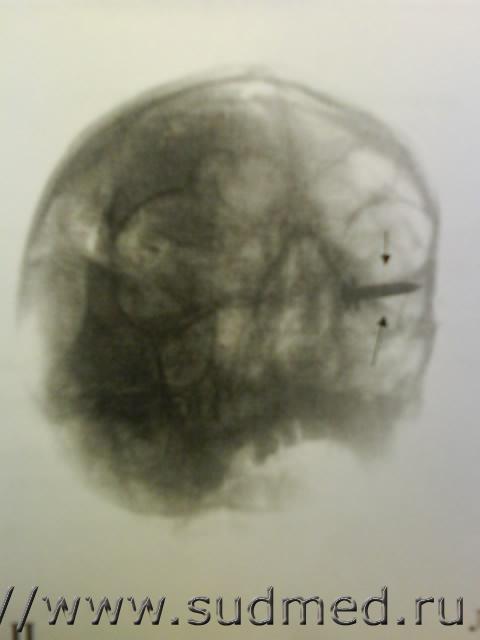

Обнаружил давнешние (со времен интернатуры) фотораграфии рентгенограмм со случаев самоубийств из строительных пистолетов.

Эскизы прикрепленных изображений

Судебная медицина - Прикрепленное изображение Судебная медицина - Прикрепленное изображение Судебная медицина - Прикрепленное изображение